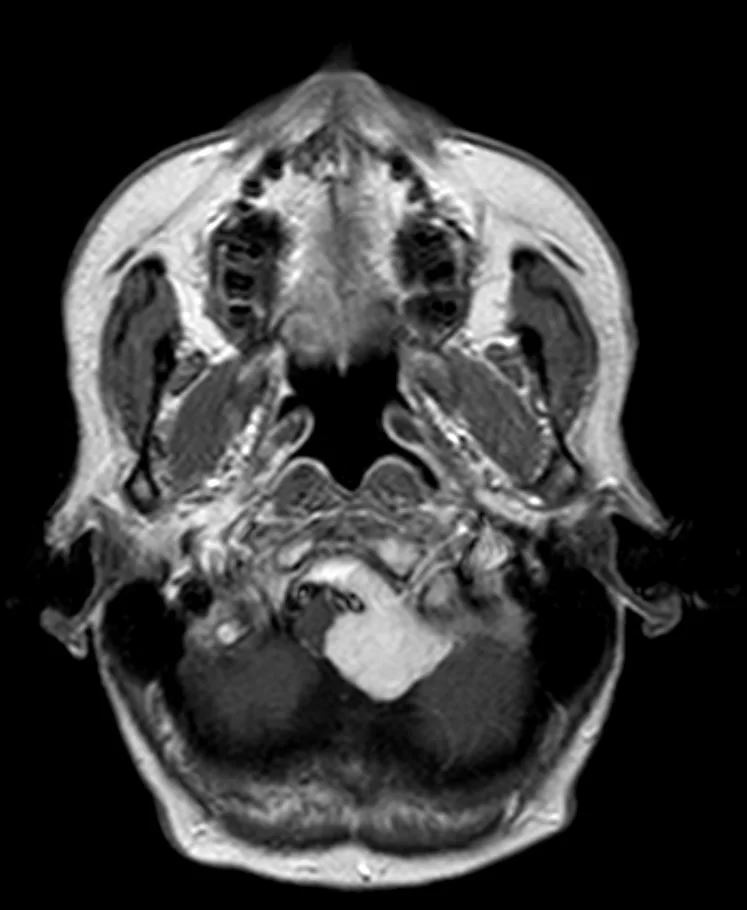

Ο προεγχειρητικός έλεγχος ανέδειξε μηνιγγίωμα της κρανιοαυχενικής συμβολής με εγκολεασμό σημαντικών αγγειακών και νευρικών δομών και επέκταση προς την αντίθετη πλευρά.

Πρόκειται για ένα εξαιρετικά απαιτητικό χειρουργείο λόγω της θέσης του όγκου. Παρόλο που πρόκειται για μια καλοήθη βλάβη (μηνιγγίωμα), ο όγκος αναπτύσσεται στο ύψος του ινιακού τρήματος και εγκολεάζει πολύ σημαντικές νευραγγειακές δομές. Επιπλέον, η μορφολογία του όγκου είναι εξαιρετικά σύνθετη, μια και επεκτείνεται έμπροσθεν του στελέχους του εγκεφάλου στην απέναντι (δεξιά) μεριά.